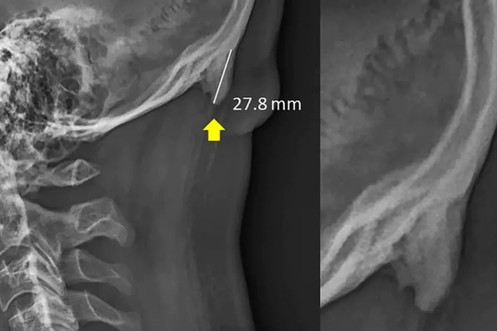

Unsere Handy-Sucht lässt uns Hörner wachsen – kein Witz jetzt!